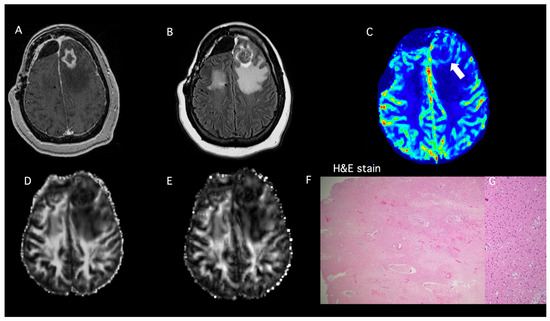

- Patient 3

| Patient ID | DTI-FA | DTI-CL | DSC-rCBVmax | PP-Value TP ≥ 50% PsP < 50% | Histopathology | Modified RANO |

|---|---|---|---|---|---|---|

| 3 | 0.08 | 0.03 | 2.02 | 1% | PsP | |